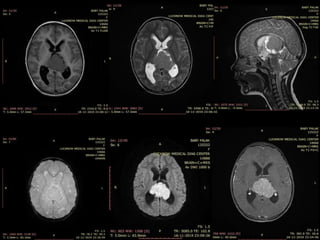

• 9yr old female patient present with headache and

numbness of limbs

• On imaging shows Relatively well define

hetrogenous enhancing mass lesion in pineal region

and concurrent suprasellar mass with

leptomeningeal spread

• Likely Diagnosis is GERMINOMA

• HPE is awaited